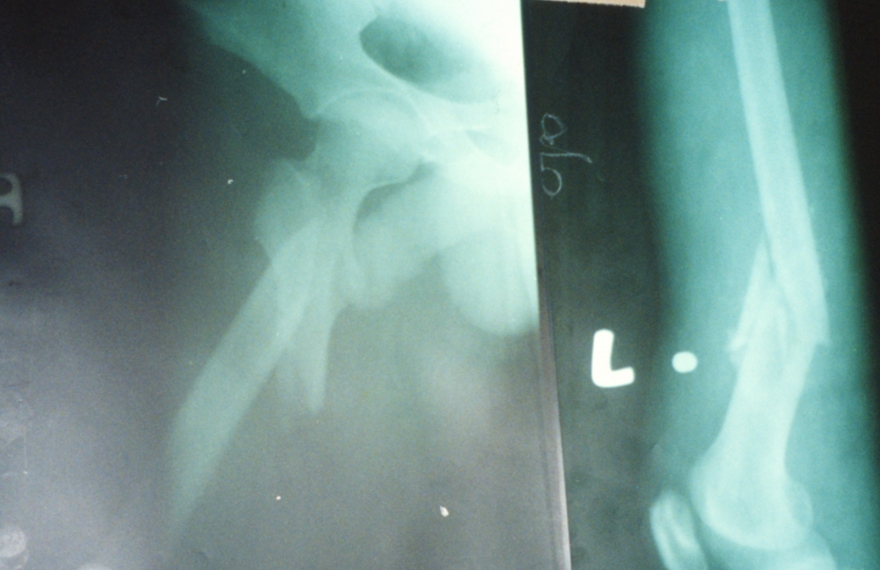

Durchschuss beider Oberschenkelknochen

Röntgenbild nach beidseitiger Osteosynthese. Patient bewegt beide Beine wieder ohne Einschränkungen.